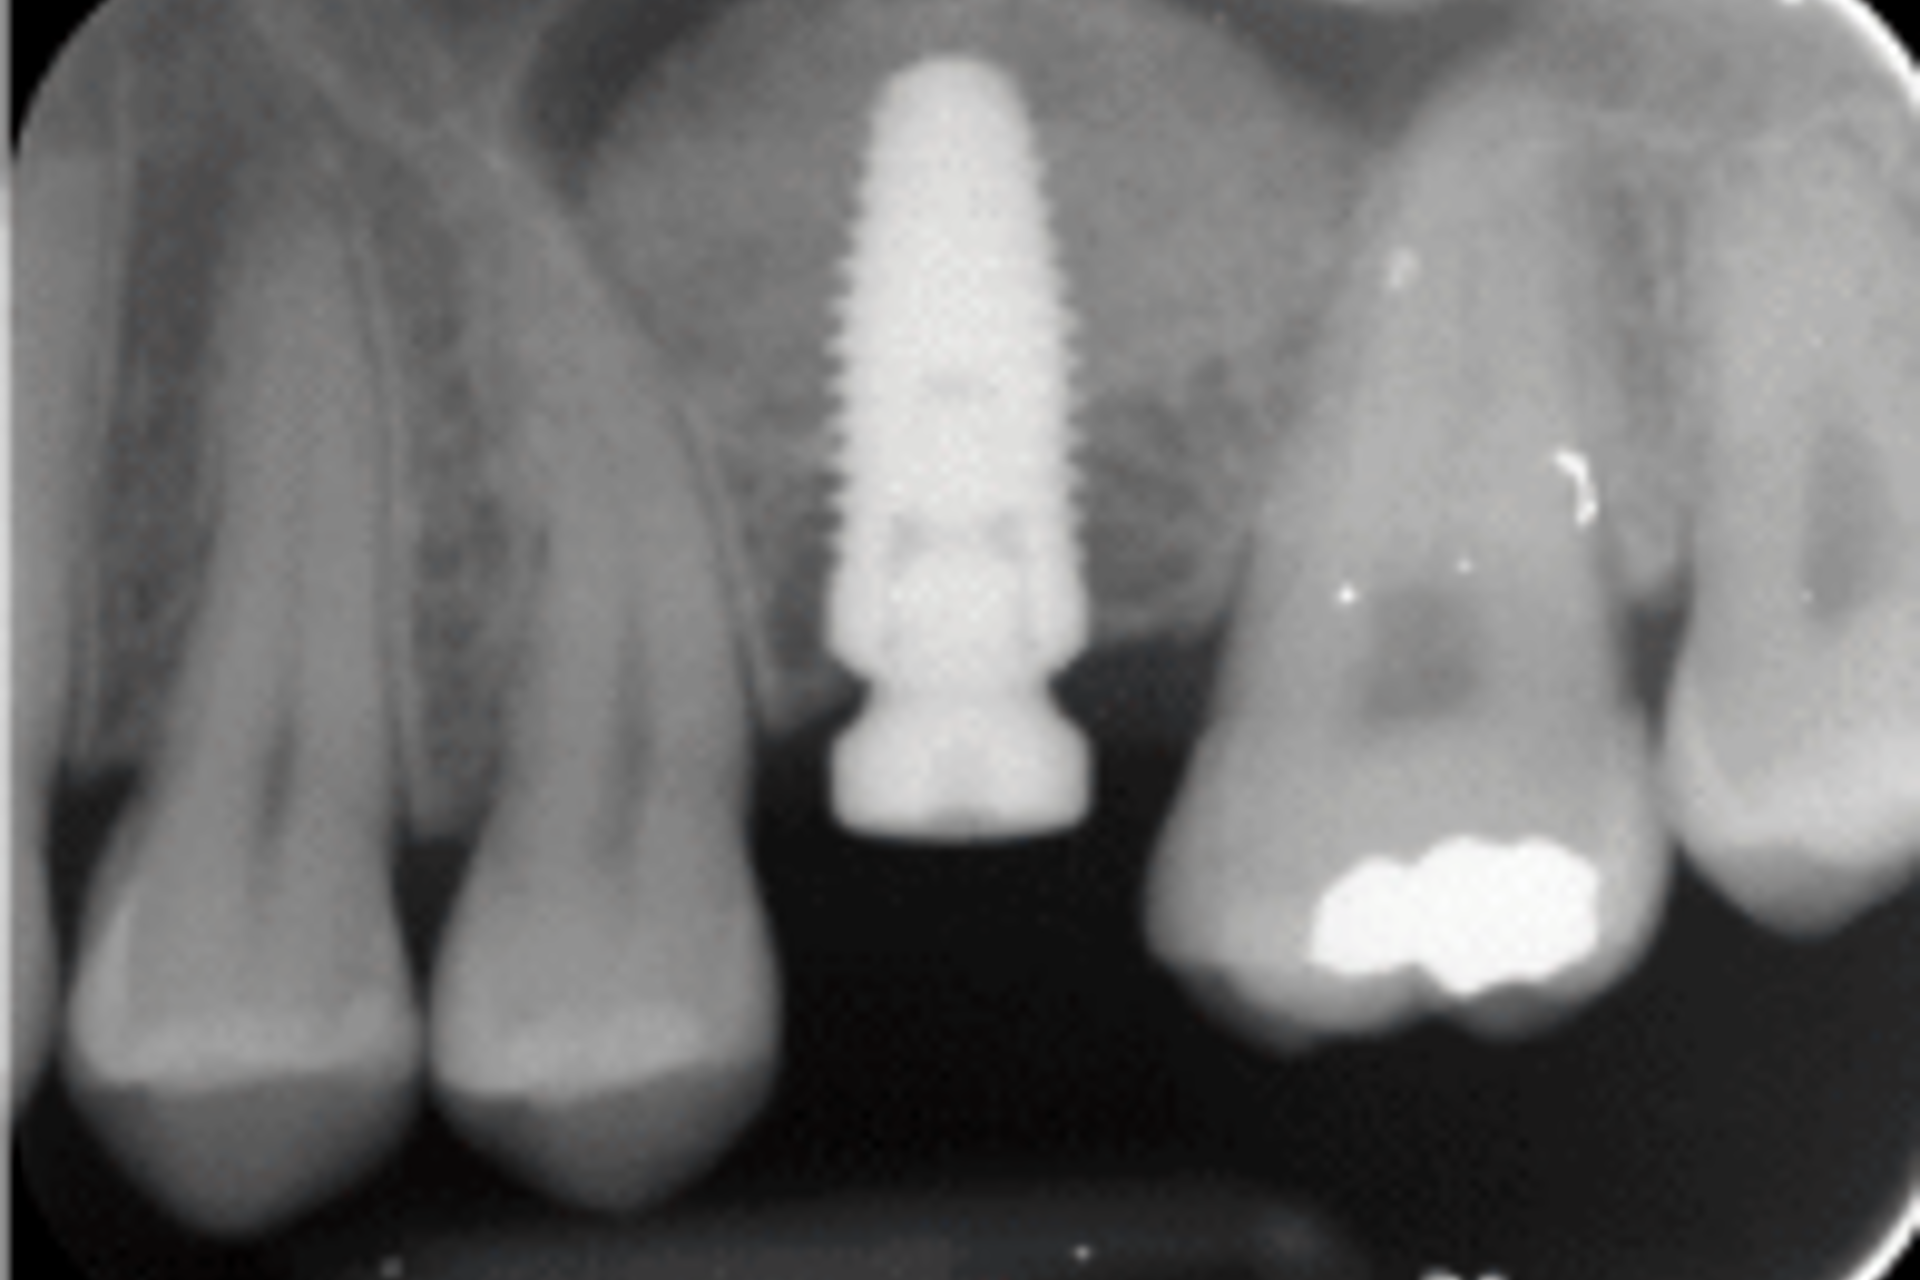

Image below shows implant placement with sinus lift and use of bone graft.

It is also often necessary to have to graft bone into the maxillary sinus, the sinus in your upper jaw, when dental implants are placed in the back area of the upper jaw and there is insufficient bone (Figure 15D), to support the dental implant because the maxillary sinus (an air space) takes up some of the jawbone.